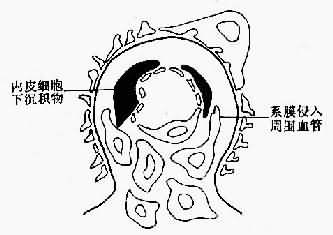

图12-14 膜性增生性肾小球肾炎Ⅰ型示意图

肾小球系膜增生并侵入周围毛细血管,血管壁增厚,基底膜内侧内皮细胞下有电子致密沉积物